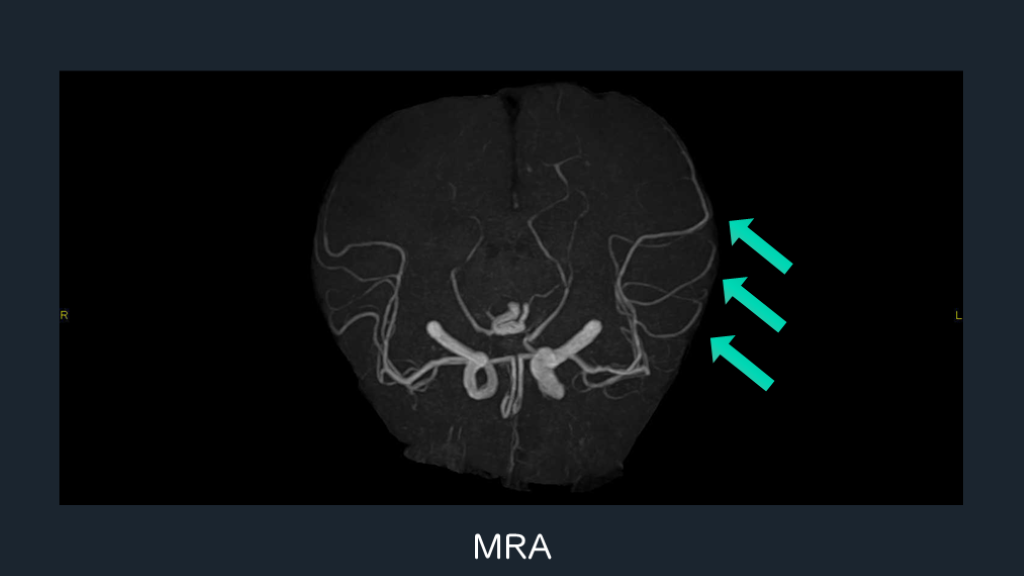

J Korean Soc Magn Reson Med. 2012;16(2):142-151. てんかん重積状態(Status Epilepticus, SE)におけるMRIのArterial Spin Labeling(ASL)法 SEでDWIで信号変化がなくても、ASL追加で異常所見が得られる。+ASLで追加の診断的情報が得られる。 Acta Epileptol. 2023;5:23. MRI ASL

灌流画像は役に立つ。脳梗塞で撮影したときも意識して評価する。 還流画像がてんかん発作の画像的な証拠として役に立つ。 発作時:過灌流所見が得られる。Perfusion CTもしくはMRIのASL法。 てんかん発作を考えたいときには意図して+ASLを追加する。 DWI+MRAも併せて注目する。 脳梗塞疑いでperfusion CTを撮った時も、意識して評価する。 解説

MRI ASL

MRA